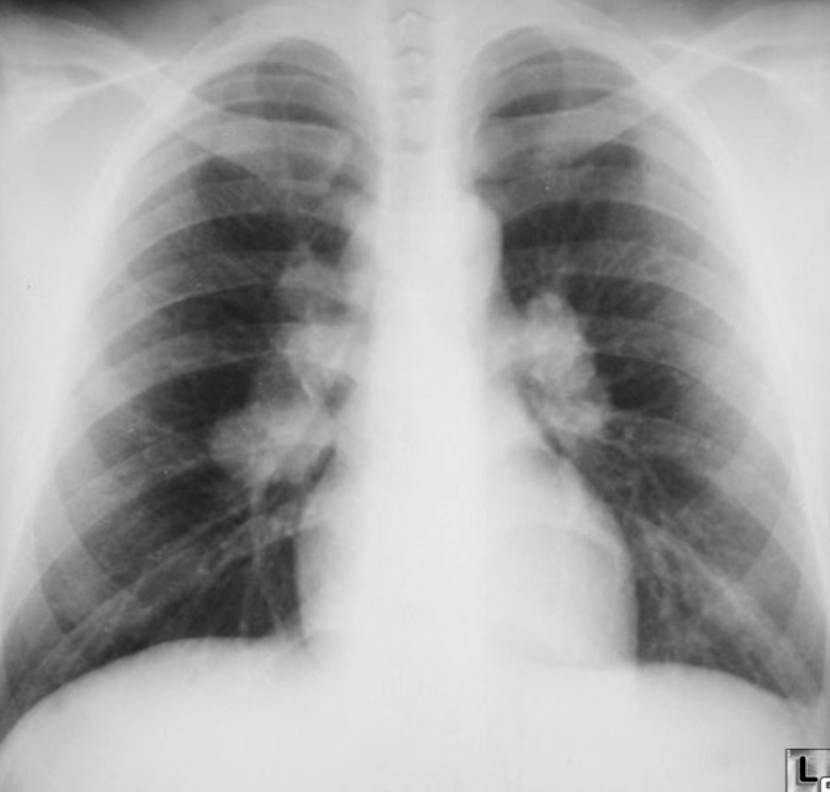

What is the abnormality in CXR? Hilar lymphadenopathy (enlarged lymph nodes in the hila of both lungs)

-

What is the most likely diagnosis? Sarcoidosis; lump

Bilateral Hilar Lymphadenopathy: Causes

| Category | Causes |

|---|---|

| Sarcoidosis | Sarcoidosis |

| Infection | * Tuberculosis * Fungal infection * Mycoplasma * Intestinal Lipodystrophy (Whipple’s disease) |

| Malignancy | * Lymphoma * Carcinoma * Mediastinal tumors |

| Inorganic dust disease | * Silicosis * Berylliosis |

| Extrinsic allergic alveolitis | * Such as bird fancier’s lung |

| Less Common Causes | * Churg-Strauss syndrome * Human immunodeficiency virus * Extrinsic allergic alveolitis * Adult-onset Still’s disease |